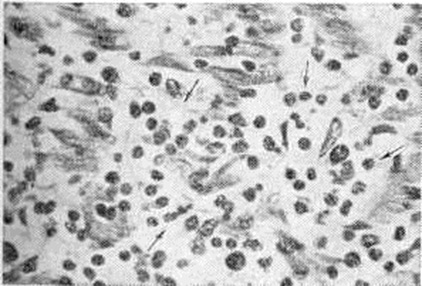

При экспериментальном Миокардит установлены нарушения окислительно-восстановительных и энергетических процессов в миокарде. Метаболические нарушения сопровождаются очаговыми и диффузными морфологический реакциями, которые дают возможность выделить паренхиматозный, воспалительно-инфильтративный, некротический, гигантоклеточный и смешанный варианты экспериментального Миокардит Наряду с очаговым кардиомиоцитолизом (рисунок 1, а), отёком и лимфогистиоцитарными инфильтратами в интерстиции (рисунок 1, б) наблюдается выраженная реакция антиген—антитело и с помощью меток выявляются В-лимфоциты и фиксированные антитела. Подострый и хронический варианты экспериментального Миокардит морфологически характеризуются мозаичностью и сочетанием воспалительных изменений с атрофией, гипертрофией и склерозом в миокарде. В эксперименте показана обратимость острого и подострого вариантов Миокардит, особенно под влиянием экспериментальной фармакотерапии. На моделях экспериментального Миокардит апробирован ряд средств, оказавшихся эффективными для лечения Миокардит у людей: противовирусные препараты (интерферон, кутизон, ремантадин), антибиотики, вакцины и сыворотки (противодифтерийная, противоменингококковая, противогриппозная), иммуно депрессоры (имуран), ненаркотические анальгетики (бруфен, индометацин), гипосенсибилизирующие и противовоспалительные препараты, анаболические средства.